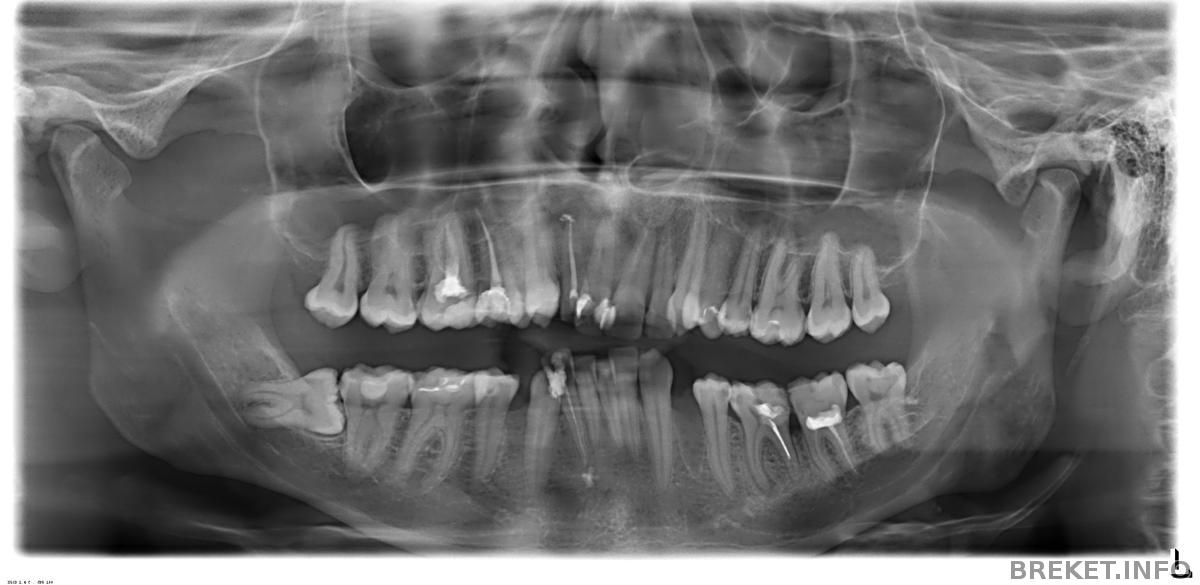

Панорама после удаления 8-ки и перелечивания каналов депульпированных зубов: